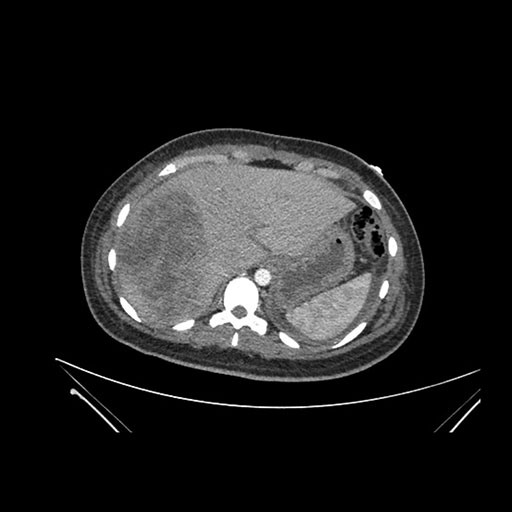

Imaging Analysis

Look through the patient's CT scan to identify any areas of concern for the necessary procedure.

Axial Arterial

Axial Venous